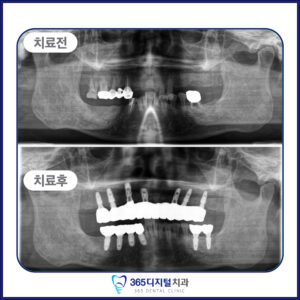

임플란트는 단순히 인공치아를 심는 것이 아닌,

환자의 삶의 질을 회복하는 진료라고 생각합니다.

오직 정밀한 진단과 정직한 진료만이

좋은 결과로 이어진다는 믿음으로

한 케이스, 한 환자에 깊이 집중합니다.

계획된 진단과 세밀한 설계,

그리고 환자 개인의 구강 구조에

맞춘 접근이 중요합니다.